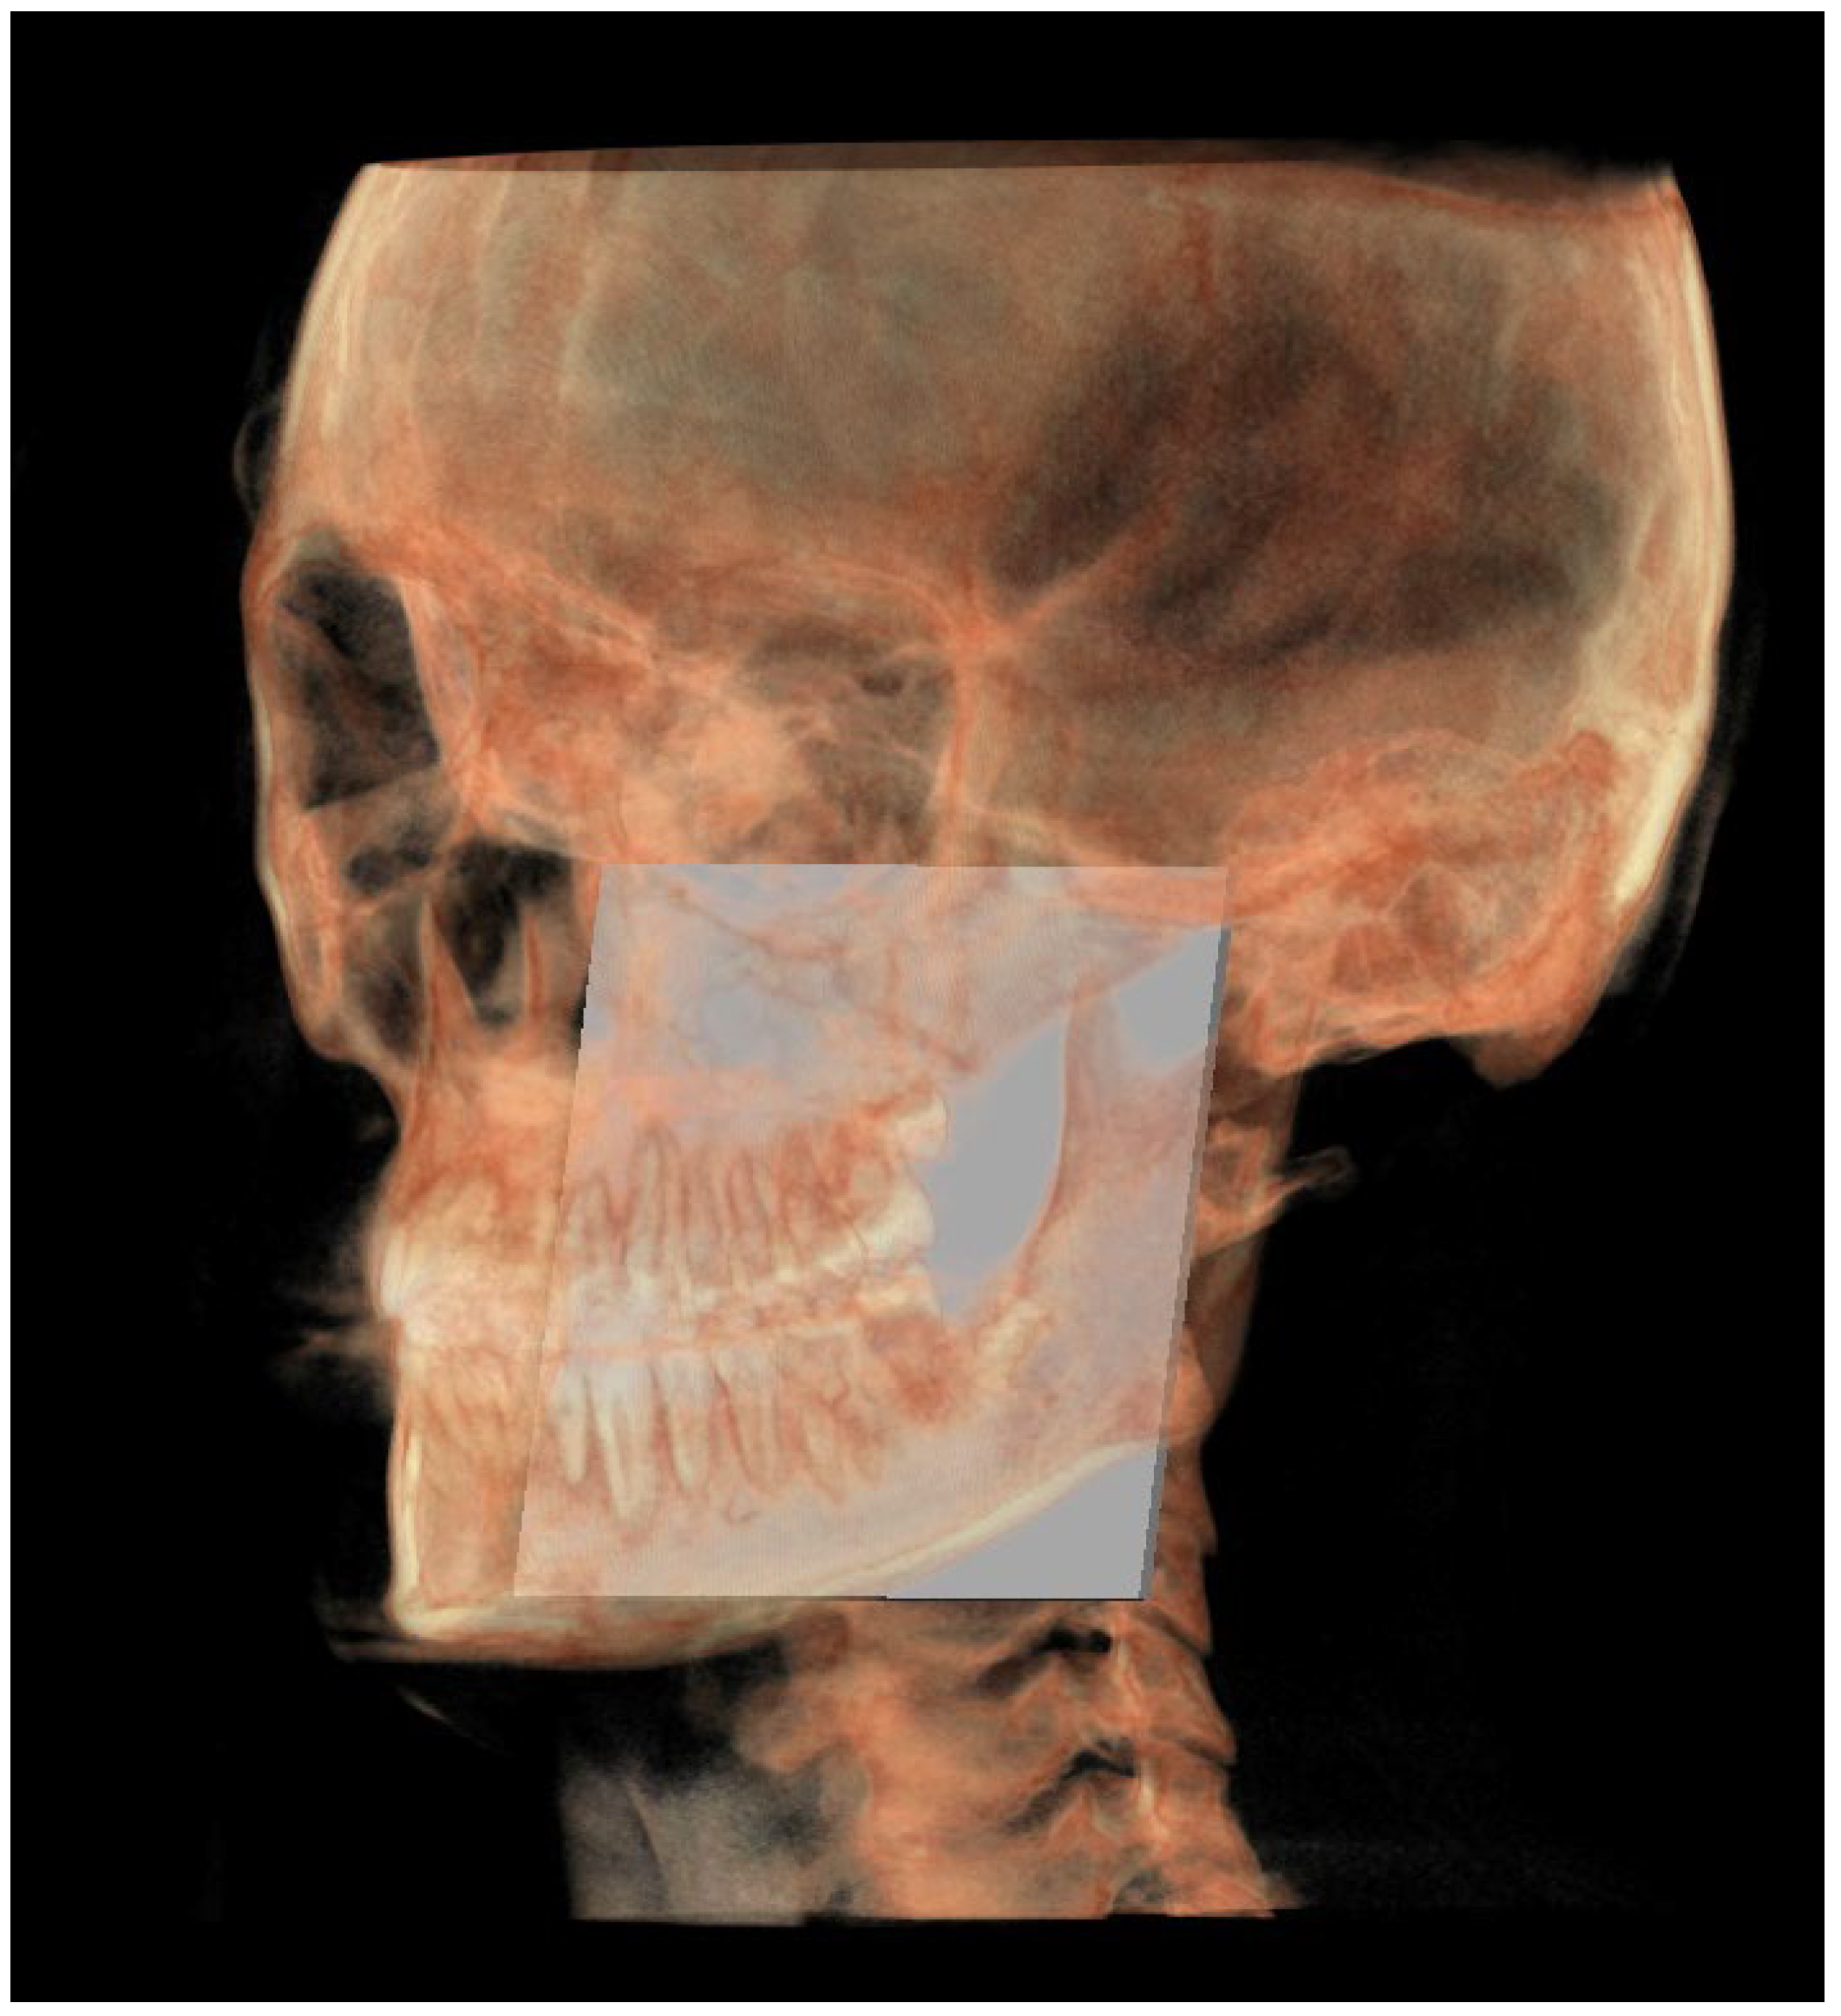

A representation of all 3D individual track planes (Figure 7).

The following image shows a comparison between the neutral (blue) and individual (white) tracks (Figure 17).

Figure 17. All the planes of the individual track (white) and neutral track (blue).